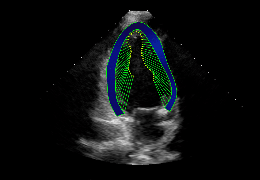

ART-Plan™ Artificial Intelligence Contouring